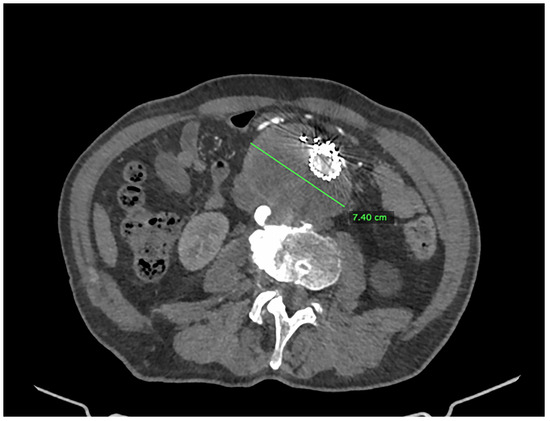

We present the case of an 82-year-old male patient who appeared in the emergency department due to progressive weakness and abdominal pain (2024). Due to a drop in blood pressure to 80/40 mmHg, a continuous infusion of norepinephrine was initiated. The hemoglobin level was approximately 5.1 g/dL. His medical history included generalized atherosclerosis, renal failure, and a thoracoabdominal aortic aneurysm (TAAA) treated with endovascular aneurysm repair (EVAR) using stent-graft implantation 4 years earlier (2020). At that time, the angio-CT scan revealed an aneurysm starting just below the celiac trunk, extending to the superior mesenteric artery (SMA) and both renal arteries (RAs). The maximum diameter of the aortic aneurysm was 51 mm; however, the left common iliac artery measured 41 mm in diameter, an indication for thoracoabdominal stent graft implantation. The aortic aneurysm itself was completely free of mural thrombus. The patient had also experienced a heart attack 16 years earlier and a transient ischemic attack (TIA) 2 years earlier. Following the stent graft implantation, he underwent multiple successful interventions to address endoleaks. One year after implantation, endovascular treatment with embolization coils was performed to eliminate leakage from the lumbar artery (LA) (2021). Three years post-implantation, he was admitted to address leakage from the inferior mesenteric artery (IMA) using embolization coils as well (Figure 1) (2023). In 2024, an X-ray and CT scan revealed a rupture in a branch of the stent graft located in the SMA in its middle part, along with an enlarged aneurysm sac (74 mm) due to the fracture and leakage (Figure 2, Figure 3, Figure 4 and Figure 5). The angio-CT scan did not reveal any contrast extravasation beyond the vessel wall. However, significant contrast leakage was visible in the area of the visceral arteries within the aneurysm sac. The implanted device was the Zenith t-Branch Thoracoabdominal Endovascular Graft, and the ruptured branch was identified as the Bentley BeGraft (Bentley InnoMed GmbH, Hechingen, Germany). Urgent surgical intervention was performed. Intraoperative angiography (IA) showed a breach in the continuity of the BeGraft material within the SMA, with contrast leakage into the aneurysm sac (Figure 6 and Figure 7). To address the leakage and restore the continuity of the SMA branch, an additional BeGraft Plus 8 × 57 mm was implanted into the damaged branch. Subsequent IA and control CT scans confirmed the elimination of leakage, restoration of stent graft continuity, and revascularization of the SMA (Figure 8, Figure 9 and Figure 10). The surgery was completed without complications, and the patient was discharged home in good general condition. The patient returned for follow-up 3 weeks after the last intervention. An angio-CT examination was performed, revealing no enlargement of the aneurysm sac (74 mm), confirming the elimination of the endoleak, and demonstrating successful revascularization of the SMA. Ongoing follow-up will be continued.

Figure 5. Ruptured superior mesenteric artery branch of stent graft—curved planes. The fractured site is marked with an arrow. Panel (A)—first projection, panel (B)—second projection. Pre-interventional Angio-CT Curved MPR, arterial phase.